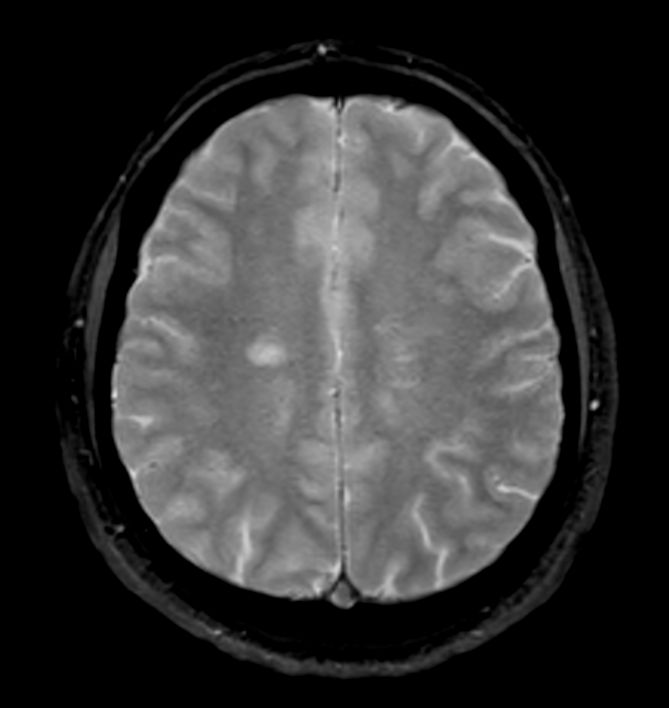

Brain - White matter lesions

Fast and high quality brain imaging for a patient with white matter lesions. AI based SmartSpeed is utlized to shorten scan time without compromise in image quality. Advanced 3D TSE imaging technique are used to acquire high resolution data in multiple directions in only one single scan.

Axial T2w TSE